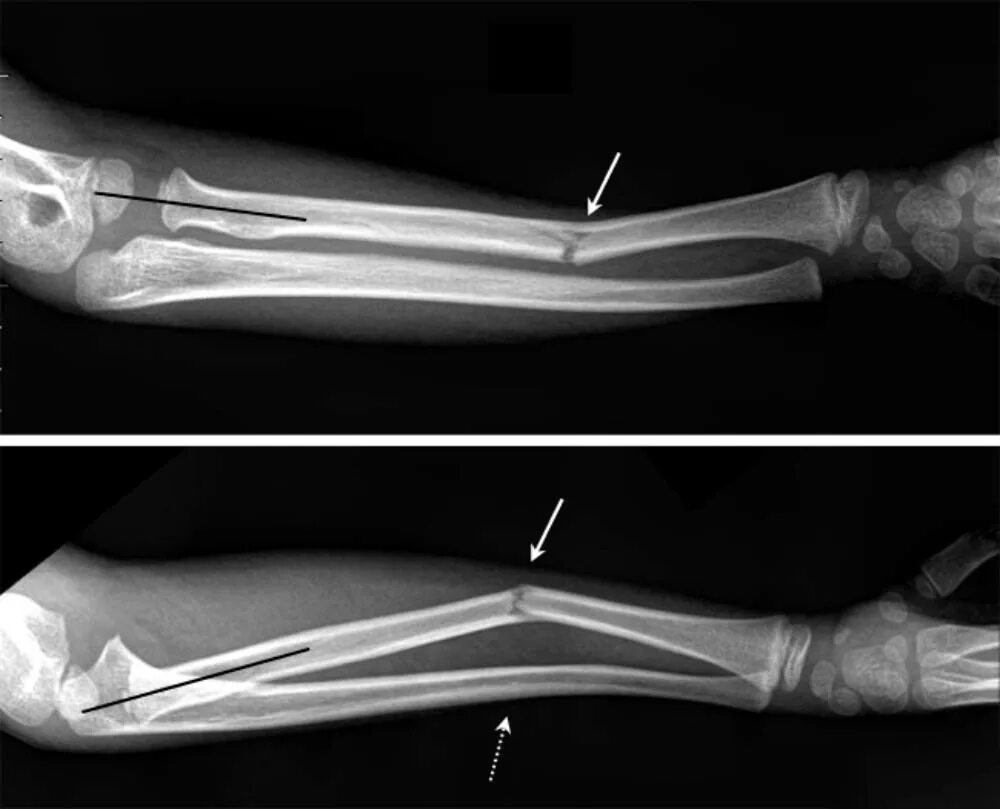

Перелом смещение локтя